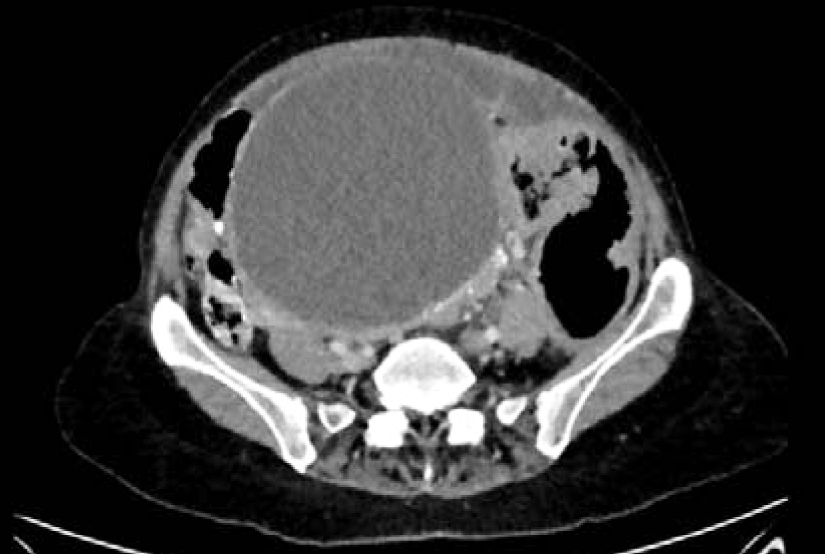

She underwent bilateral salpingo-oophorectomy, omentectomy, pelvic and para-aortic lymphadenectomy, resection of tumor implants of the bowel and colon, with optimal cytoreduction. Official pathologic tissue diagnosis consistent with borderline serous ovarian carcinoma, pT3 N1 MO, consistent with FIGO stage IIIC. Patient ultimately had a total abdominal hysterectomy and resection of multiple retroperitoneal lymph nodes including low and high periaortic, inter aortocaval, celiac trunk, hepatic artery and retropancreatic lymph nodes. There was evidence of metastatic low-grade serous carcinoma involving multiple matted lymph nodes (Figure 10 and 11).

Figure 10: CT scan abdomen and pelvis. Enlarged matted portocaval lymph node 1.7 cmx2.6 cm.

Figure 11: CT scan abdomen and pelvis. Enlarged lymph node 1.cm x 1.5cm between the aorta and inferior vena cava.